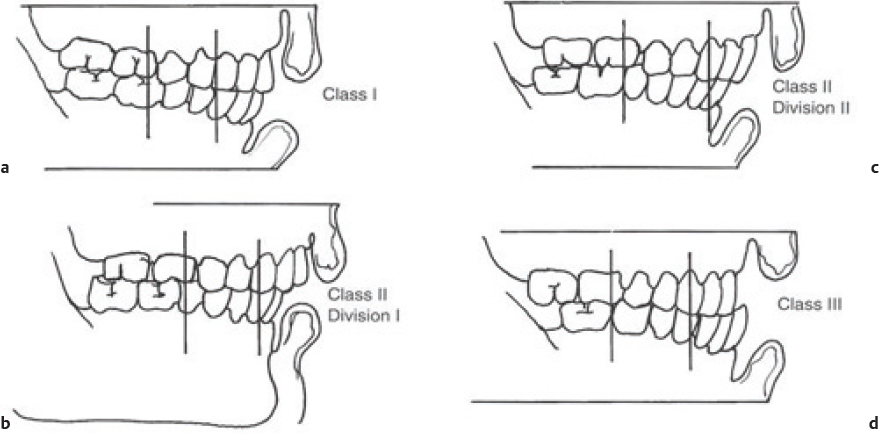

Preoperative occlusal evaluation should be performed by having the patient bite down into his or her best fit occlusion. Careful examination of the dentition will identify loose or avulsed teeth. If teeth are missing, chest imaging should be performed to ensure that they have not become airway foreign bodies ( Fig. 65.3 ). Fig. 65.4 demonstrates variants of adult occlusion. Ideal occlusion or Angle’s Class I occlusion occurs when the mesialbuccal cusp of the maxillary first molar rests in the buccal groove of the mandibular first molar ( Fig. 65.4a). Class II occlusion occurs when the mesialbuccal cusp rests anterior to the buccal groove. There are two divisions of Class II occlusion. In the first division ( Fig. 65.4b ), the incisors demonstrate an overjet. In the second division, the incisors are palatally tilted to compensate for the abnormal occlusion; this results in a more normal appearing dental relationship anteriorly ( Fig. 65.4c ). Class III occlusion occurs when the mesialbuccal cusp rests posterior to the buccal groove ( Fig. 65.4d ). 12 Wear facets on the teeth may offer hints to the preinjury occlusion in patients with poor dentition or longstanding malocclusion. An anterior open bite suggests possible subcondylar fracture(s). Grasping and attempting to manipulate the fractured mandible segment may assist in assessing instability of the fractured segment. Bilateral fractures may result in an unstable central mandible fragment that when posteriorly displaced results in tongue prolapse and airway obstruction. Anterior traction on the tongue with a heavy suture or towel clamp can restore and maintain the airway acutely while deciding on more definitive airway management such as intubation or tracheotomy. 13